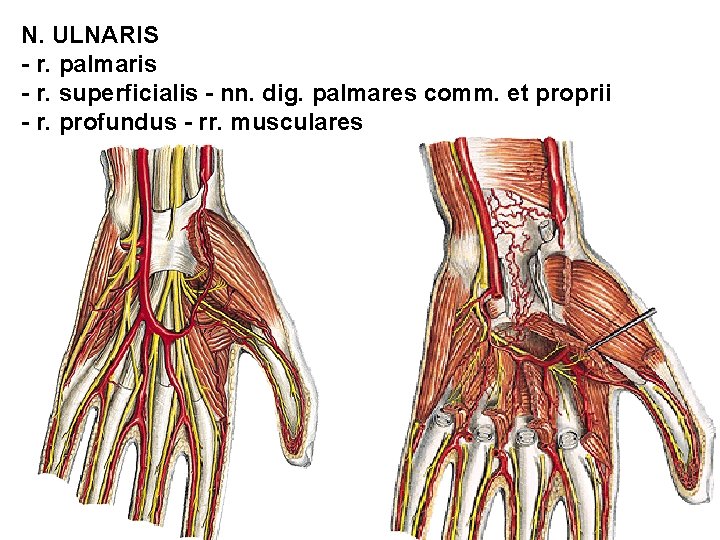

N. ULNARIS - r. palmaris - r. superficialis - nn. dig. palmares comm. et proprii - r. profundus - rr. musculares